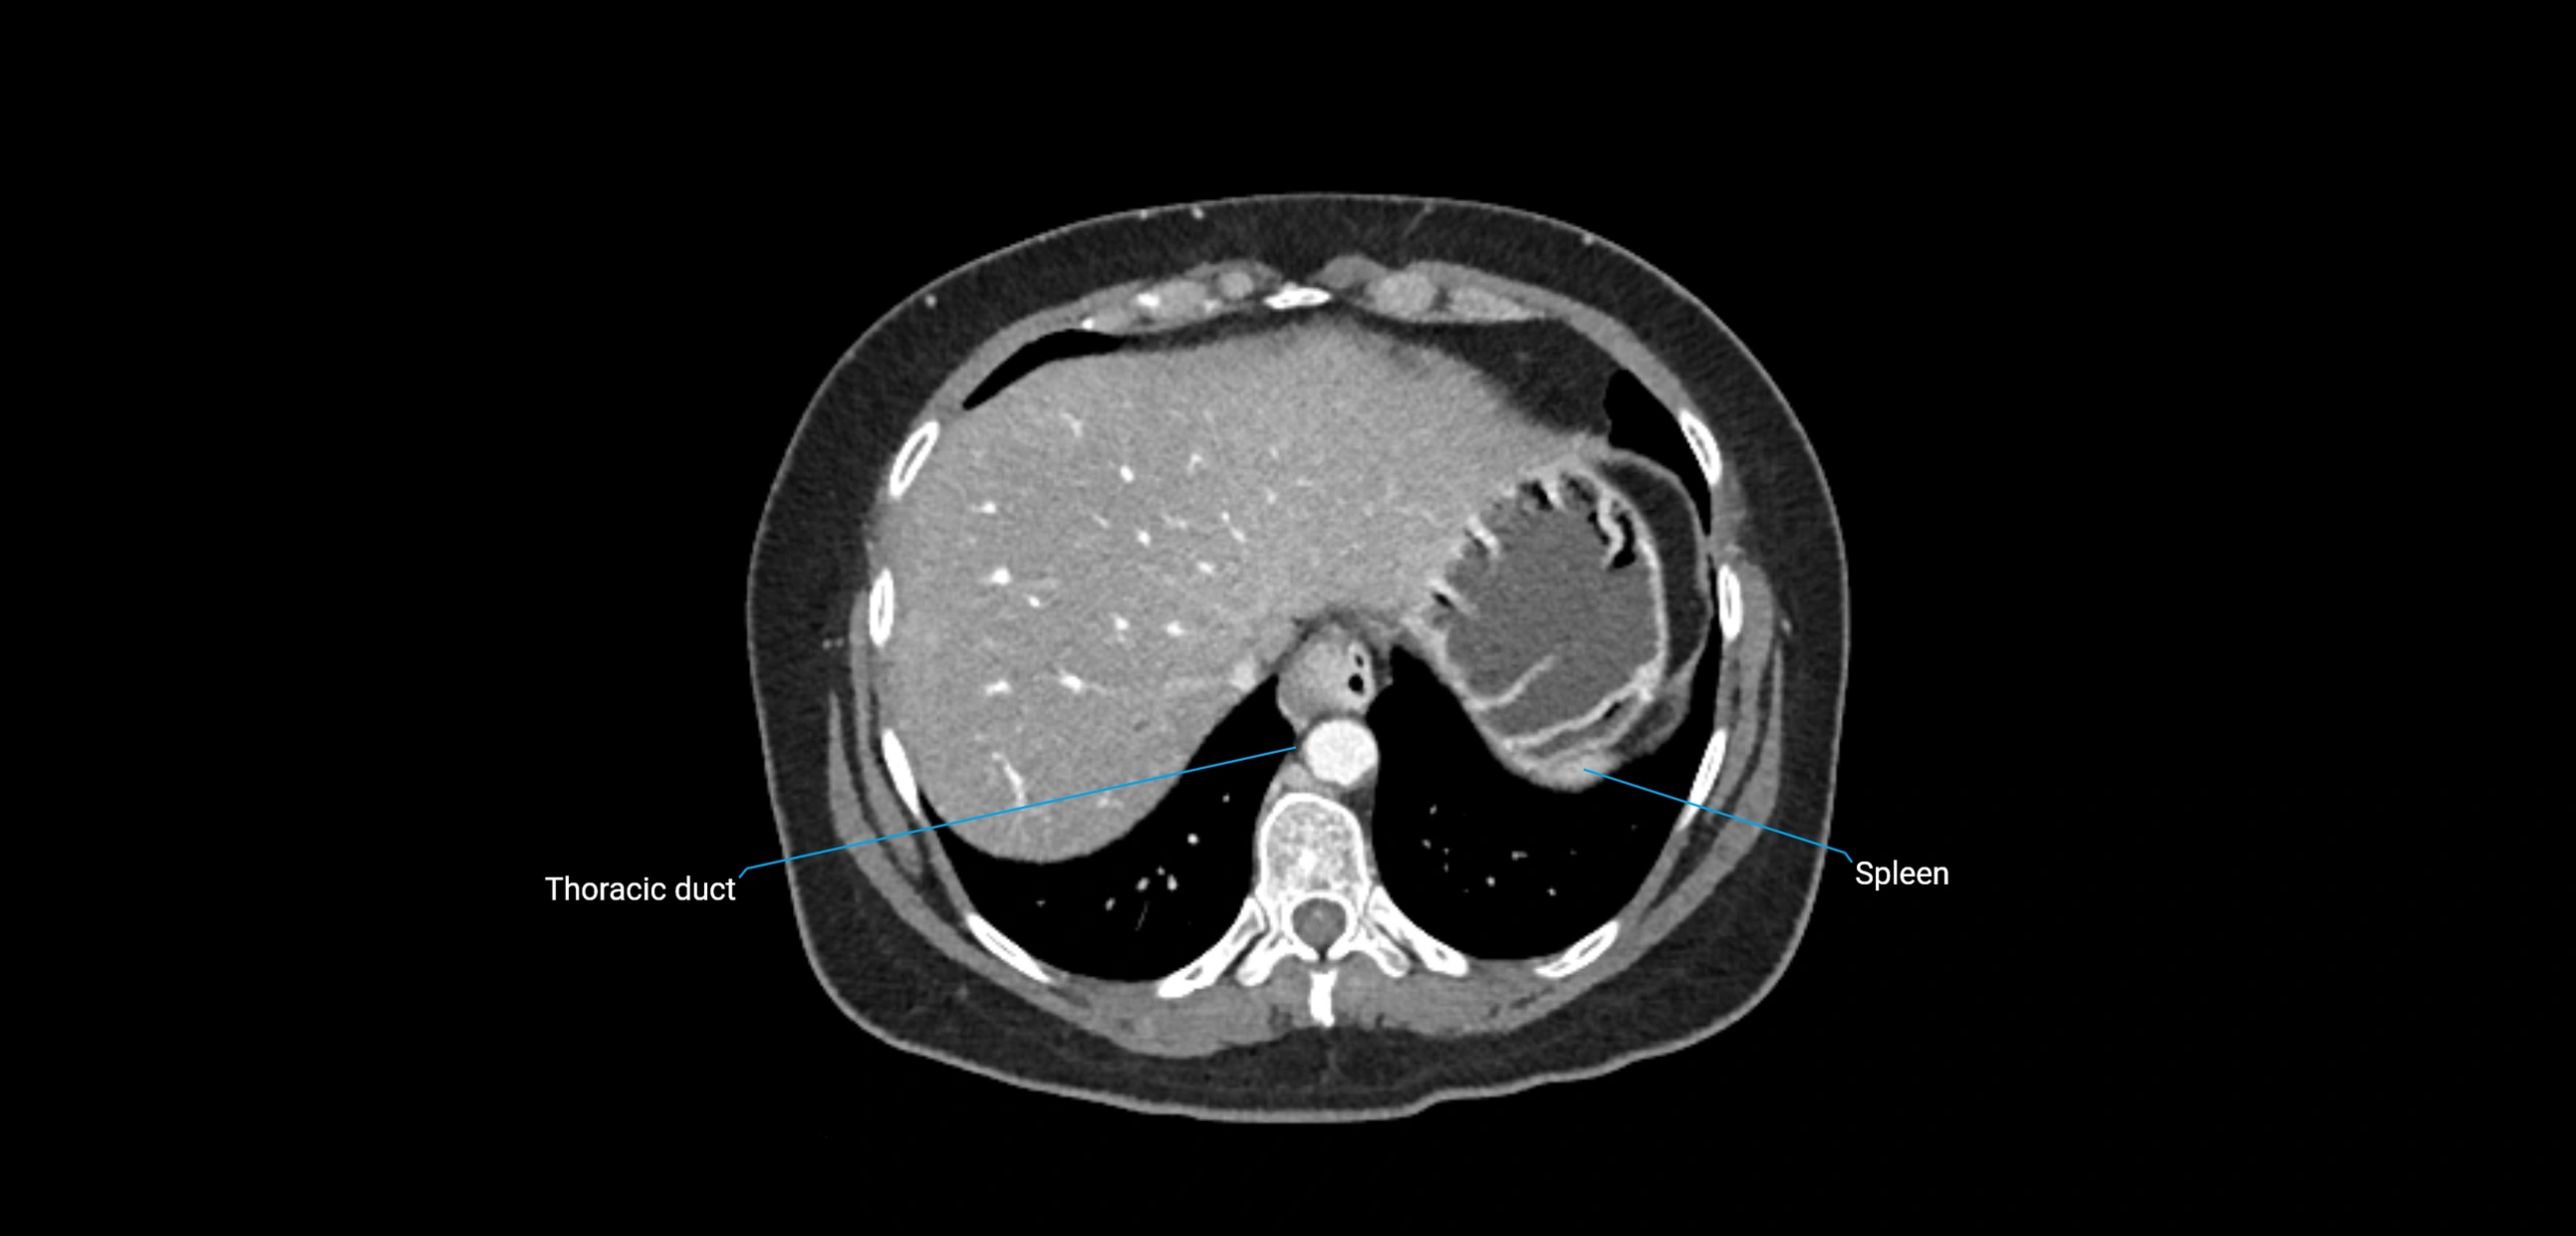

CT image

image